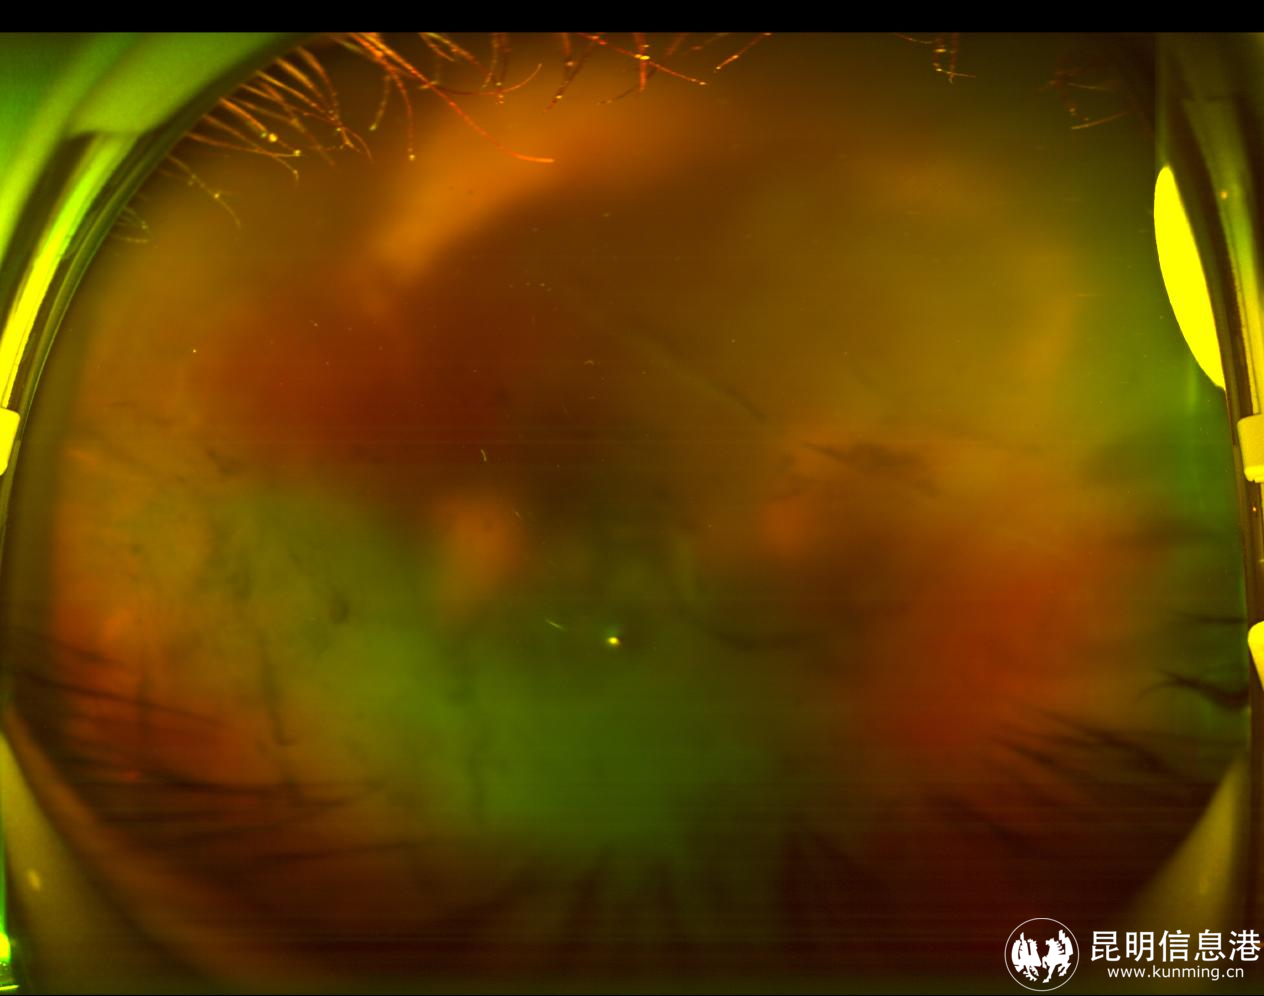

圖為眼底彩圖(術(shù)前):玻璃體積血后眼底細(xì)節(jié)窺不清 昆明艾維眼科醫(yī)院供圖